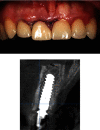

Anterior aesthetic zone implant placement and tooth restoration can be a quite challenging procedure. Modern technology offers new tools that can help maximize results in both aesthetic and functional ways. The socket-shield technique, as described by Hürzeler et al., boosted with the 3D diagnostics, digital planning, and 3D printing, could provide a valuable alternative to traditional approaches. This case report describes a clinical workflow for an efficient anterior implant-prosthetic restoration.